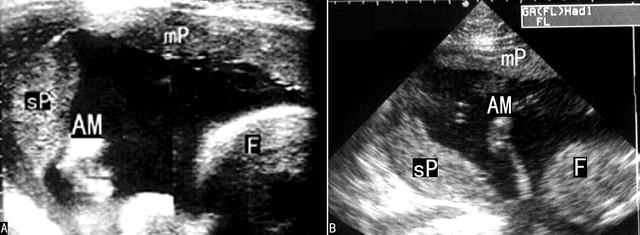

超声显像检查(2D-US)在早期妊娠和中期妊娠可以显示多叶PL和副叶PL,亦可无明显异常发现。典型的多叶PL和副叶PL多在子宫腔增大到一定程度以后显示,在羊膜腔内除显示一个主PL外还可显示一个或数个PL回声,厚度多较正常薄,表面不光滑(图2),仔细检查可以显示其与主PL之间由血管连接;有时多叶PL在位置上并无明显分离,但PL实质内显示完整的分隔回声。多数情况下多叶PL和副叶PL难以在产前得到明确诊断;彩色多普勒血流显像(CDFI)显示PL之间的血管连接有助于对多叶PL的诊断。

图2副叶胎盘声像图

需要注意分叶或副叶PL和宫颈口的关系,以排除副叶PL前置或其连接血管前置。常发生的是胎儿常规产前检查显示正常位置的PL后忽视了对多叶PL或副叶PL的观察。笔者曾遇到一例主叶PL位置正常、忽视了副叶PL前置而出现大流血的病例。应特别强调的是中晚期妊娠、观察到正常位置PL的孕妇,在进行产前2D-US时也应要求在适度充盈膀胱后进行,以便能够显示子宫下段,排除形态异常的PL前置。另外,在副PL中,PL梗死和脐带帆状附着的发生率比较高,在检查时应注意辨认。